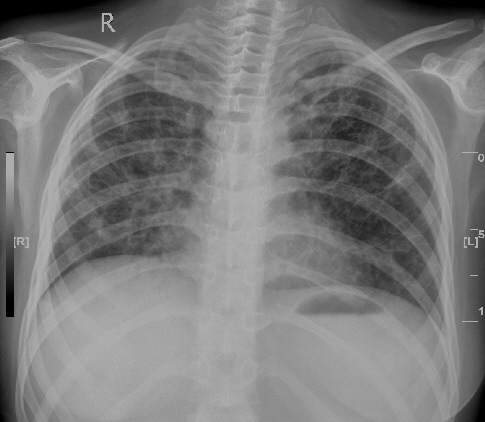

2007年6月20日胸片

2006-11正常,2007-5-9弥漫分布絮团影,2007-6-20片仅见纤维索条样影,tb吸收没这么快,考虑真菌感染可能大(绒毛癌转移及韦格氏病不支持)